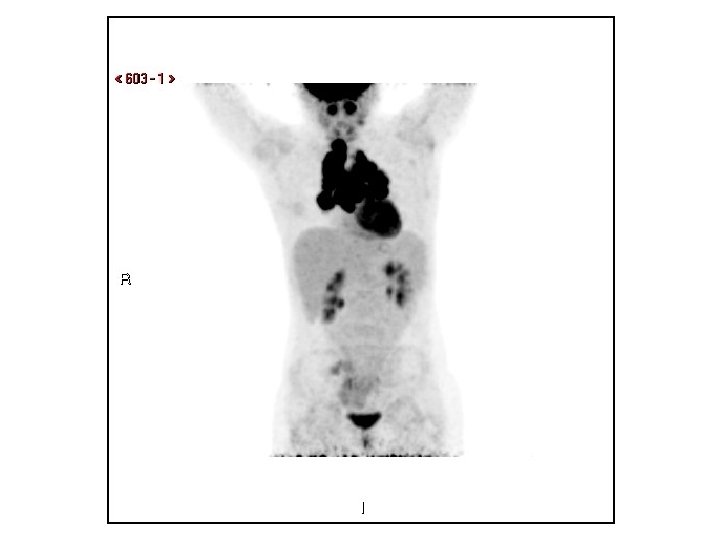

Diagnosis/Follow up Diagnosis: Mediastinal& hilar lymphadenopathy/mass Follow up • 1 st clinic visit: Imaging concerning for possible lymphoma, although no worrisome sx, history, labs, or exam findings • PET: “FDG avid mediastinal and hilar lymphadenopathy” • 2 nd clinic visit: fatigue, submandibular adenopathy • CT-guided FNA: “Atypical lymphocytes” – Flow Cytometry: “normal thymic tissue”